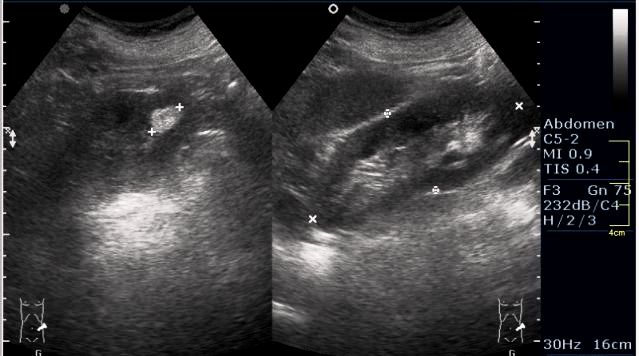

Женщина 50 лет. Жалоб нет. Обследование перед поездкой в санаторий по поводу дисфункции гепатобилиарной системы.

Случайная находка в нижней трети левой почки (не в полюсе, а по задне-медиальной поверхности).

Образование в левой почке

ПО УЗ-семиотике образование соответствует ангиомиолипоме (AML). По правилам в таких случаях необходимо выполнить КТ, доказать преимущественно жировой состав опухоли, затем проводить УЗ-наблюдение.

Согласен. Именно с таким диагнозом (ангиомиолипома) отправил на КТ. Особенностью случая ИМХО является заметный "выход" образования за контур почки (на 2/3 объема).

При ультрасонографии ангиомиолипома выглядит как округлое образование без капсулы с однородной внутренней эхоструктурой и четкими контурами; эхогенность ее чаще всего равна или чуть выше эхогенности перинефральной клетчатки [7]. Значительно реже эхогенность ангиомиолипом может быть равна эхогенности почечной паренхимы; такие опухоли состоят почти полностью из гладкомышечной ткани [8]. Иногда позади ангиомиолипомы может определяться слабая акустическая тень.